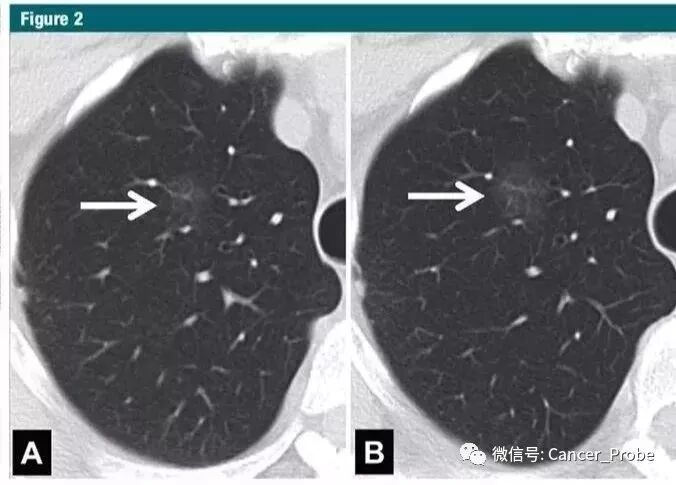

文章来源:南京市胸科医院胸外科王科平主任